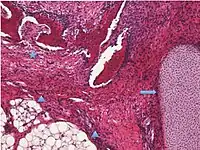

| Surface epithelial-stromal tumor | Serous tumor | 25% | 18.5% | Benign serous tumors of the right ovarian cyst are thinwalled unilocular cysts that are lined by ciliated pseudostratified cuboidal or columnar epithelium.[6] |  |